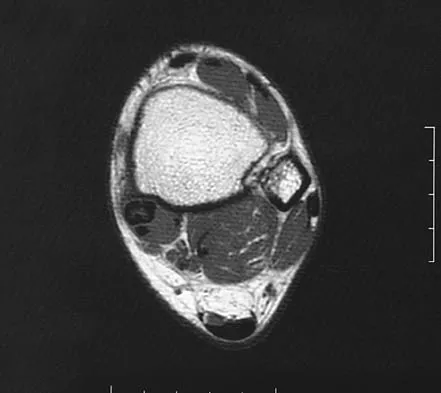

A patient has right shoulder pain. Figure 1a shows a gadolinium-enhanced transverse MRI scan at the level of the coracoid. Figure 1b shows an arthroscopic view of the anterior structures from a posterior portal. These images reveal which of the following findings?

The area shown in the arthroscopic view and MRI scan is referred to as a Buford complex and represents a normal labral variant. It consists of a thickened, cord-like middle glenohumeral ligament, a superior labral attachment of the middle glenohumeral ligament just anterior to the biceps tendon, and absence of the anterosuperior labrum. This combination of findings can be confusing and may simulate labral pathology. Mistaken repair of the lesion back to the glenoid rim can result in significant loss of external rotation. A Bankart lesion would be located at the inferior anterior glenoid rim. The subscapularis is seen anterior to the labrum. Normal variations that occur in the anterosuperior labrum can simulate pathology. Gusmer PB, Potter HG, Schatz JA, et al: Labral injuries: Accuracy of detection with unenhanced MR imaging of the shoulder. Radiology 1996;200:519-524. Griffin LY (ed): Orthopaedic Knowledge Update: Sports Medicine. Rosemont, IL, American Academy of Orthopaedic Surgeons, 1994, pp 47-63.

- Williams MM, Snyder SJ, Buford D Jr: The Buford complex: The "cord-like" middle glenohumeral ligament and absent anterosuperior labrum complex. A normal anatomic capsulolabral variant. Arthroscopy 1994;10:241-247.